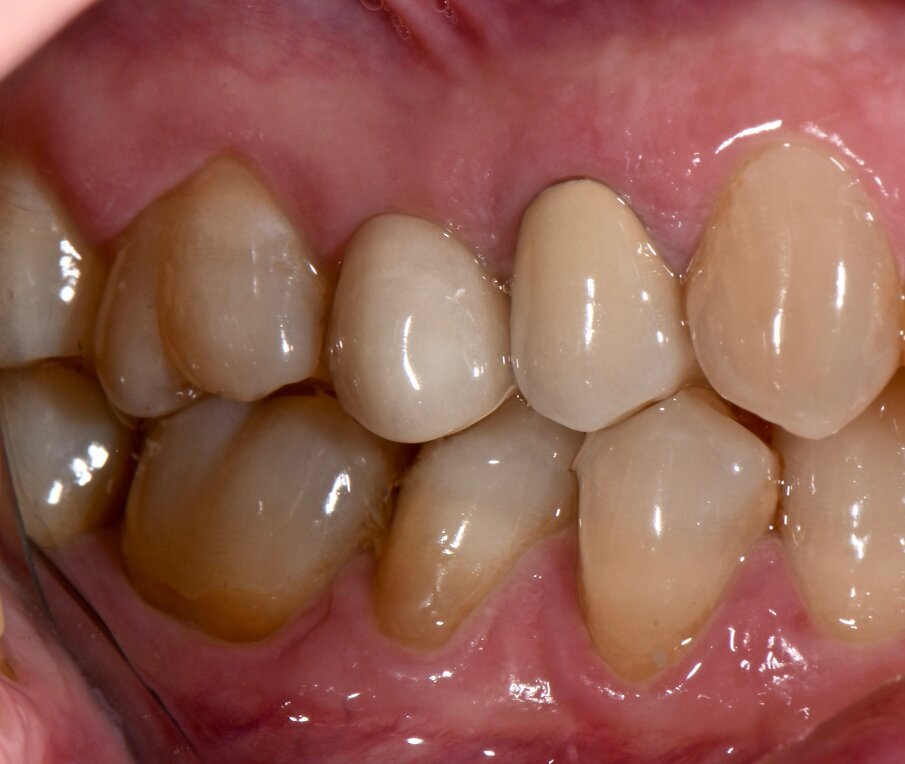

Materiali e metodi Case report Il presente case report è stato redatto in accordo con il CARE checklist (https://www.carestatement.org/checklist, consultato il 29 Gennaio 2024). Una paziente italiana di 44 anni, non fumatrice si è recata alla S.C Riabilitazione Orale Protesi Maxillo-Facciale e Implantologia Dentaria della Dental School dell’Università degli Studi di Torino nel mese di Gennaio 2023, lamentando sanguinamento gengivale durante lo spazzolamento. La paziente ha firmato un consenso informato. L’anamnesi medica della paziente non era rilevante. All’esame intraorale si evidenziava una scarsa igiene orale e la presenza di impianti in sito 15 e 25 (Figg. 1a-1c). I parametri parodontali al baseline sono stati riportati in Figura 2.

Fig. 1c - Condizione clinica al baseline: III e IV sestante.

Il Full Mouth Plaque Score (FMPS) era 71%, il Full Mouth Bleeding Score (FMBS) era 24% ed è stata osservata una profondità di sondaggio ≥ 4 mm nel 9,5% dei siti, localizzata a livello dei molari e premolari di entrambe le arcate. L’impianto in situ 15 (Nobel Replace, diametro 4,3mm, lunghezza 13mm) e l’impianto in situ 25 (Sweden & Martina SYRA, diametro 4,25 mm, lunghezza 1 mm) presentavano placca e una mucosa peri-implantare eritematosa ed edematosa. Per ciò che concerne l’impianto 15, si era riscontrata una moderata (PPD 4-5 mm) e severa (PPD≥ 6 mm) profondità di sondaggio, con una profondità media di 3.33 mm. FMBS e FMPS erano del 100%, così come riportato in Figura 2. La rilevazione dei parametri peri-implantari dell’impianto 25 aveva evidenziato PPD moderati nel 67% dei siti e una PPD severa a livello mesio-vestibolare. FMPS e FMBS erano 100%.